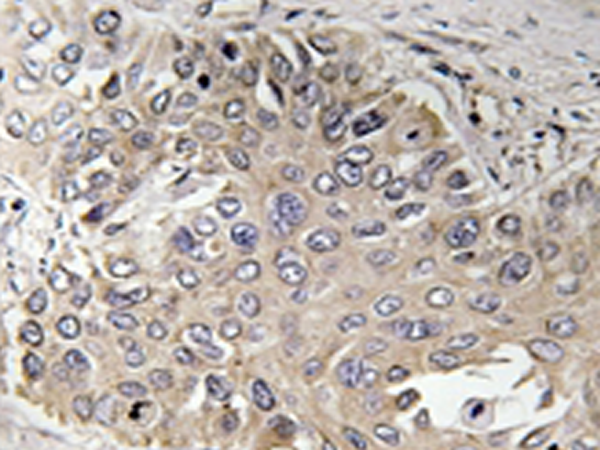

IHC positive control: |

Human lung carcinoma tissue |

IHC Recommend dilution: |

50-100 |